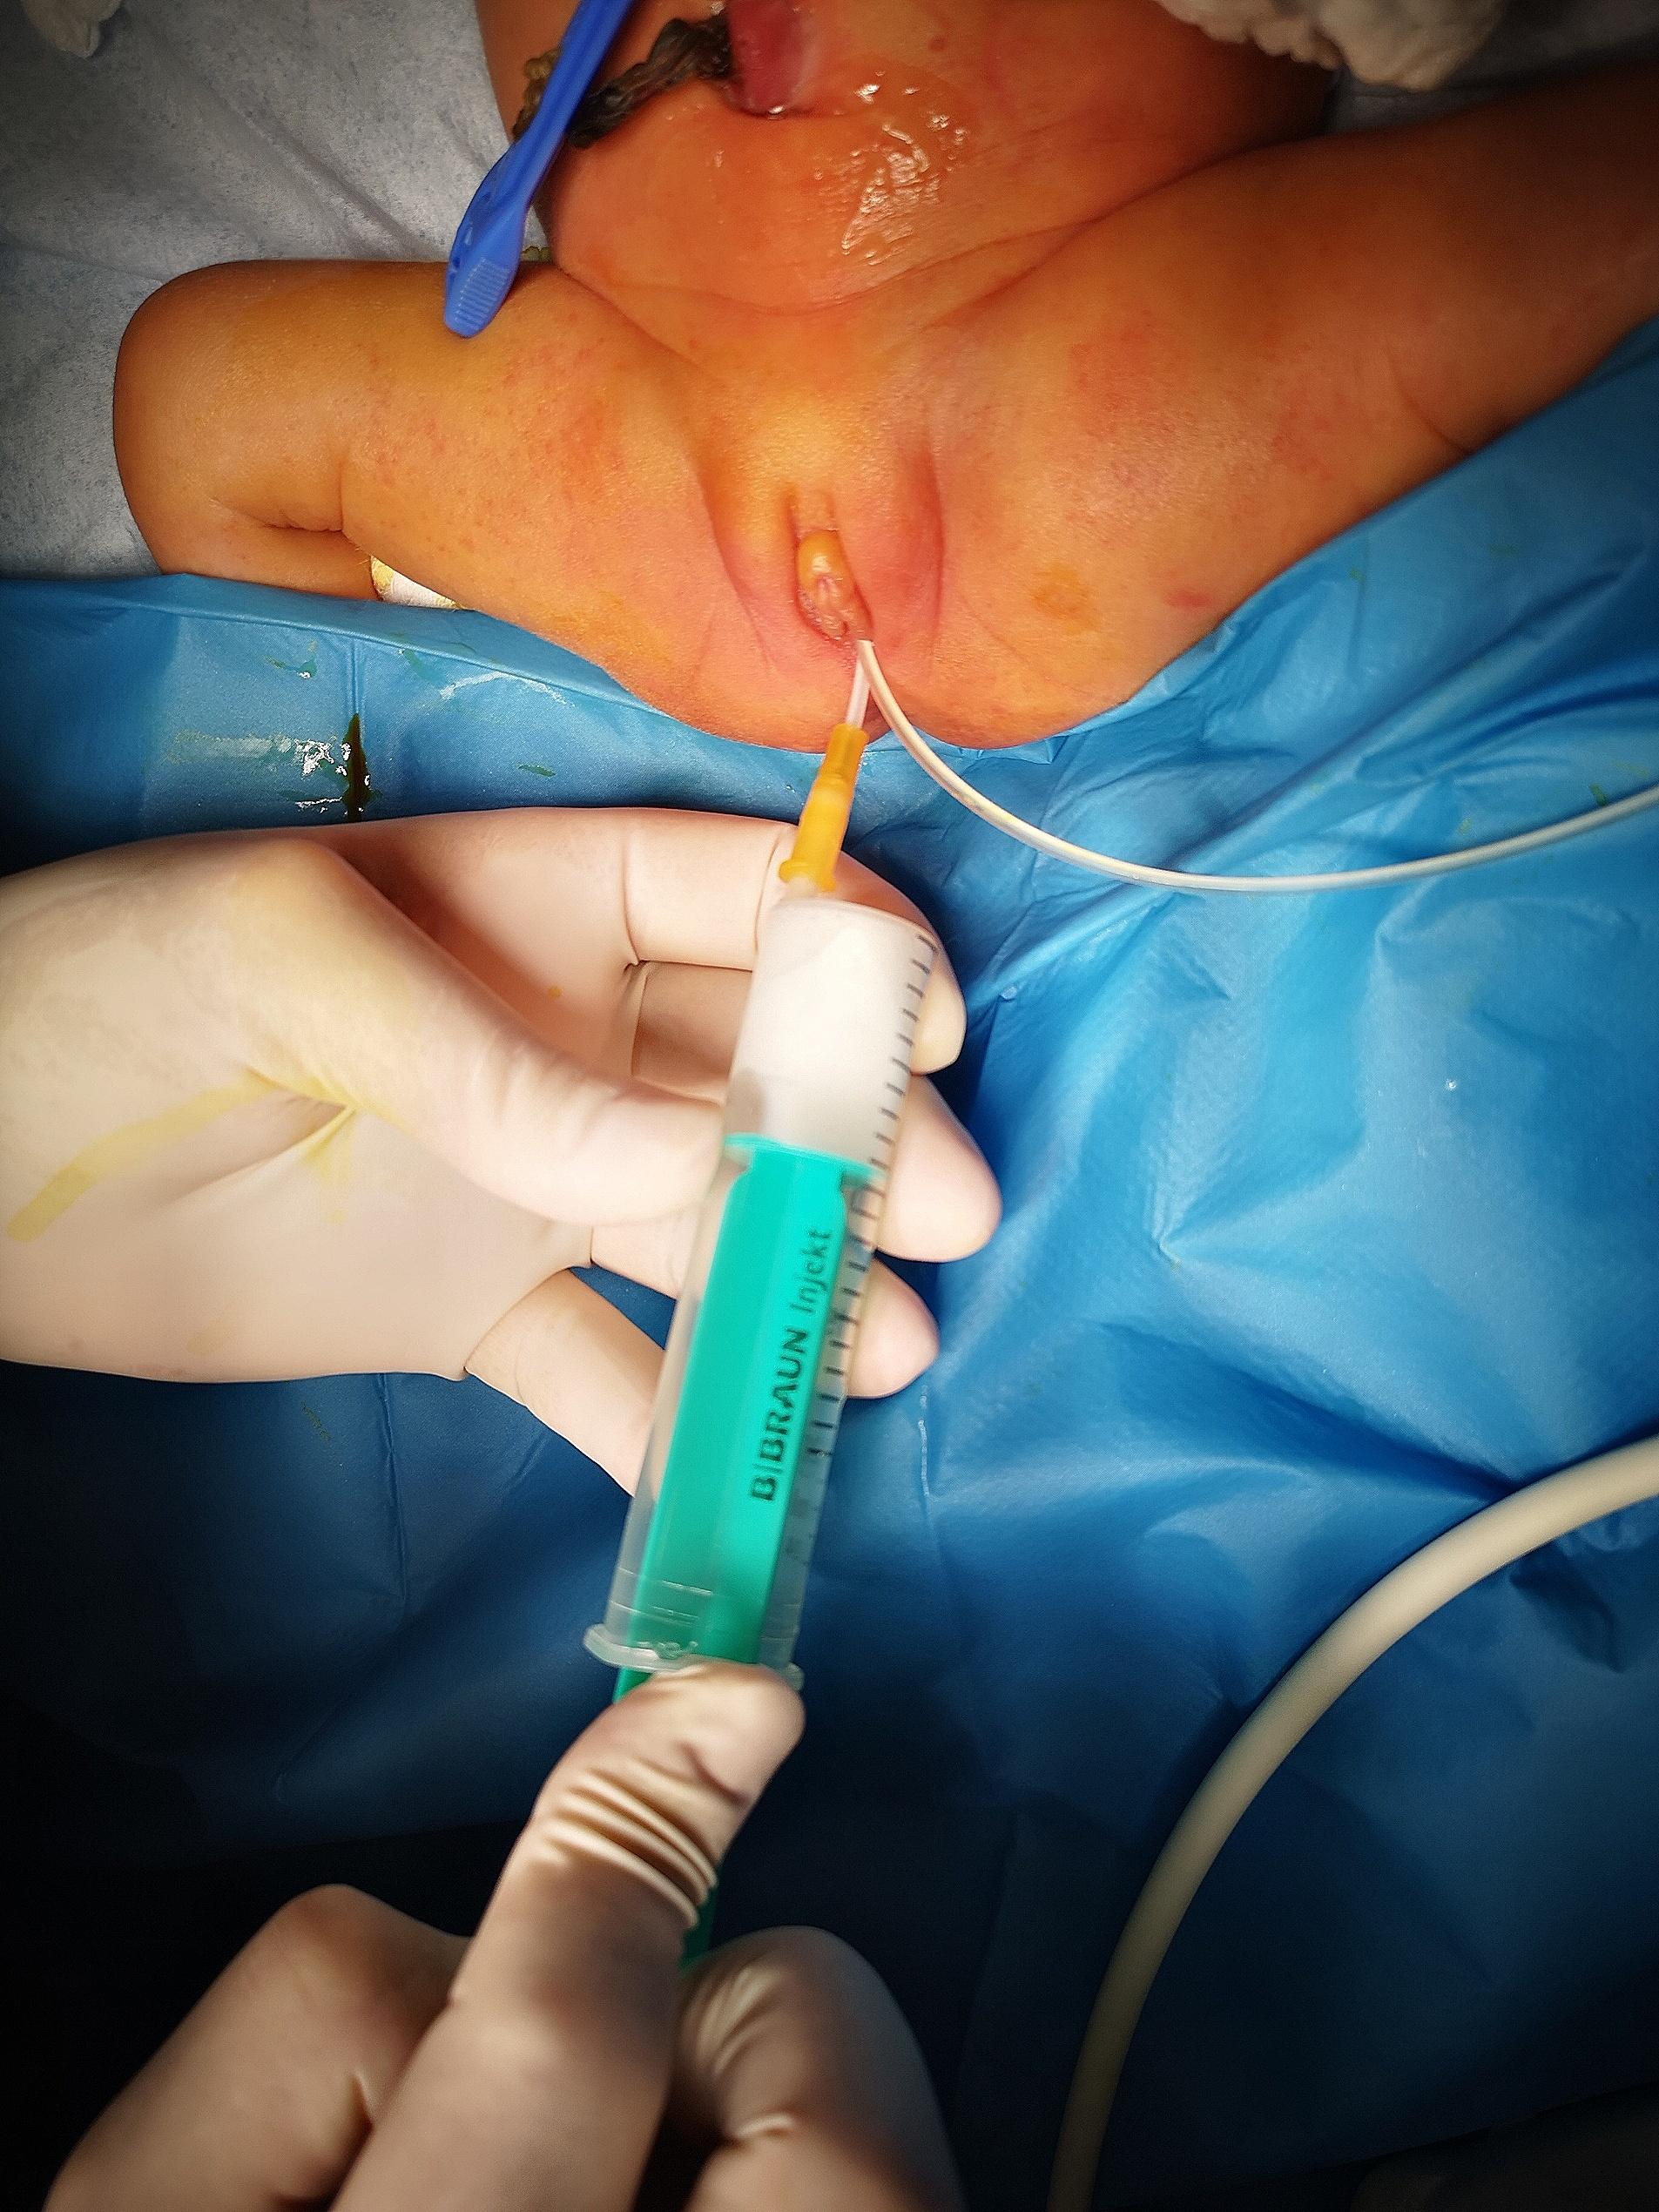

Case presentation: We present here the case of a preterm neonate who was admitted to the surgical neonatal intensive care unit for bowel obstruction. The baby did not appear septic or unwell, a small amount of meconium passed frequently, and no bilious gastric residuals occurred. Based on these findings, acute abdominal obstruction was doubtful, and the surgeon chose a conservative (watch and wait) approach. Subsequently, we performed abdominal ultrasound and magnetic resonance imaging based on unclear information about a suspicious abdominal mass raised by the gynecologist shortly before the emergency C-section. The final diagnosis was congenital hydrocolpos due to imperforate hymen. The pediatric gynecologist indicated an incision of the imperforate hymen under general anesthesia. The incision resolved abdominal distention as well as the bowel obstruction.

Conclusion: The presentation of hydrocolpos was not typical (no bulging in the vaginal introitus) in our case, and clinical symptoms implied acute bowel obstruction shortly after birth. The surgeon chose a conservative (watch and wait) approach as the baby did not appear unwell on the second day of life. Fortunately, diagnostic laparotomy was not required as the next step in bowel obstruction management. All clinical symptoms resolved after a minor surgical procedure.